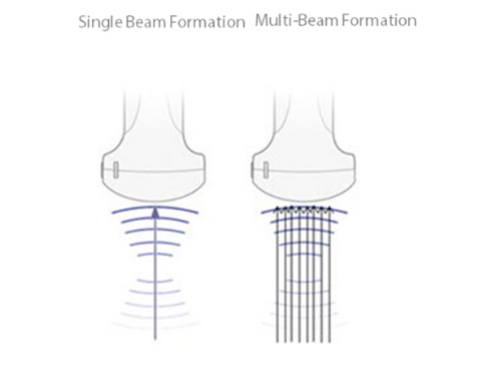

3T Transducer Technology

MindrayŌĆÖs patent transducer technology to increase image bandwidth and transmission efficiency.┬Ę Triple-matching layer design for higher sensitivity, wider bandwidth, and improved S/N.

┬Ę Total-cut design for lower cross-talk noise, better directivity, and improved lateral resolution

┬Ę Thermal-control design for better acoustic transmission